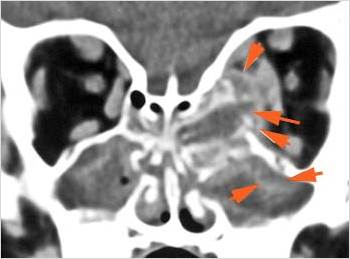

The extraconal orbital fat is abnormal. [Yes/No]

There is a subperiosteal abscess or edema along the medial wall, roof or floor of the orbit. [Yes/No]

The extraocular muscles are swollen or otherwise abnormal. [Yes/No]

There is bone erosion along the walls of the orbit. [Yes/No]

The intraconal orbital fat is infiltrated. [Yes/No]

The orbital apex and the superior and inferior orbital fissures are infiltrated. [Yes/No]